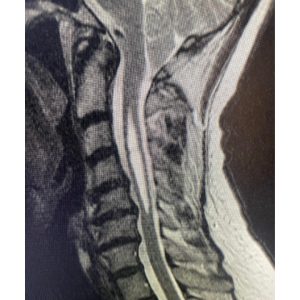

“A Chiari malformation results when a patient has too little room for their cerebellum in the back part of the skull. The cerebellar tonsils get forced down into the spinal canal. The result can be a syrinx or fluid filled cavity within the spinal cord that can cause pain, weakness and numbness. The Chiari malformation with or without a syrinx can also cause also headaches and other symptoms. Surgical treatment is most important when a syrinx is present to prevent progression of the neurologic symptoms.

These MRI scans show a patient before and after the Chiari decompression surgery that I performed. The surgery involves removing a portion of the back of the skull and the ring of C1 to relieve the pressure on the cerebellar tonsils and spinal cord. The bottom MRI was taken five years later and shows resolution of the syrinx. ”